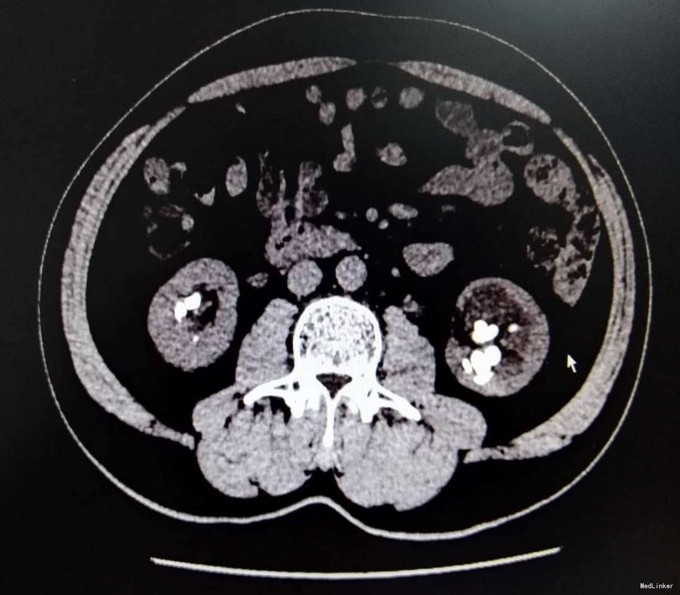

3、查体:未见明显阳性体征 4、辅助检查:外院平片:双肾多发结石;我院CTU:双肾多发结石,左侧肾盂输尿管连接处结石,并双肾积水,左肾明显,双侧肾盂、输尿管炎症。

5、诊断:肾结石(双肾多发结石) 6、治疗:入院后完善相关检查,双肾CTU:双肾多发结石,左侧肾盂输尿管连接处结石,并双肾积水,左肾明显,双侧肾盂、输尿管炎症。排除手术禁忌症后行左侧PCNL术,术后恢复良好,拔出肾造瘘管后,先出院休息,2周后返院进一步治疗